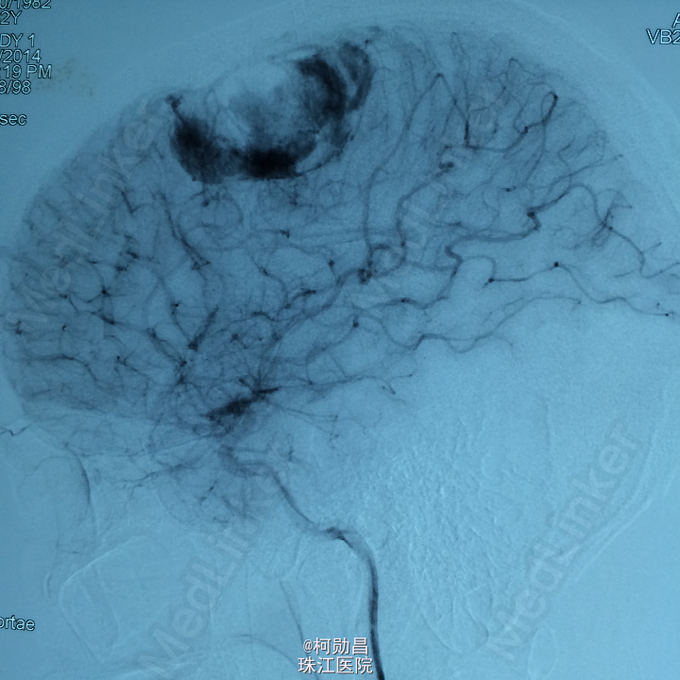

主诉:头痛伴右上肢麻木无力两个月,加重七天 病史:两个月前出现头痛,走路不稳,右上肢无力,不能持物,过去两个月曾有两次癫痫全面发作,发作时意识丧失,但无尿失禁及舌头咬伤。查头MRI示右侧顶叶占位,考虑脑膜瘤。

查体:巴氏征阳性,左侧肢体感觉减退,肌力正常,余无特殊阳性。 辅助检查:查头MRI示右侧顶叶占位,考虑脑膜瘤。

诊断:左侧顶叶占位 处理:行DSA检查,提示肿瘤染色,予PVA颗粒行血管内栓塞治疗。

术后再予开颅手术治疗,书中见供血动脉闭塞,出血量少。